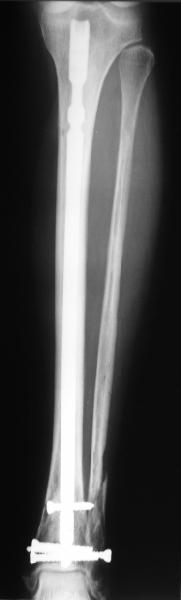

Проксимальный и дистальный переломы tibia

Направили к нам пациентку 35 лет с переломом дистального отдела костей голени.

У нас сделали снимок сзахватом обоих суставов - еще и проксимальный метафиз сломан. Чем бы у вас фиксировали такой перелом? Как его правильно закодировать по классификации АО?

Можно либо как два перелома - 41A+42B. А можно как один сегментарный 42С.